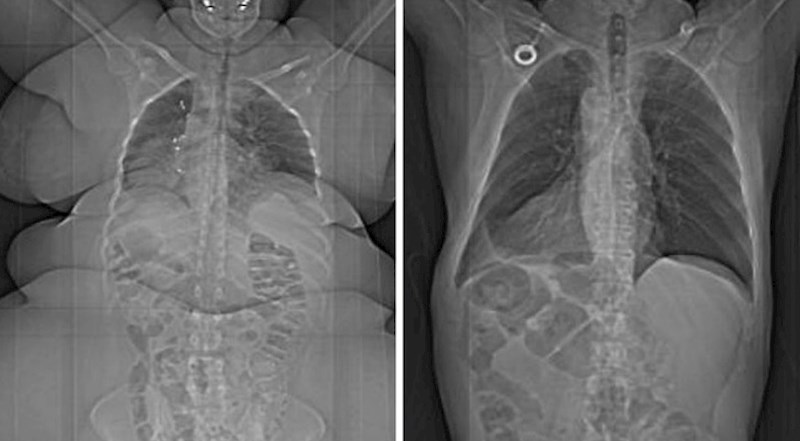

Pretila osoba vs. osoba normalne težine